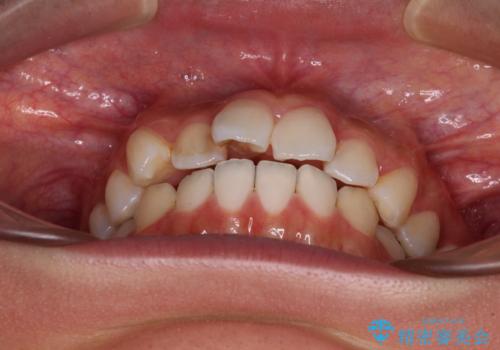

- 前歯のデコボコと口元の突出感を気にして来院された患者様です。

口元の突出感が認められ、更には左右で異なる咬合状態であったため、下顎右側は第二小臼歯を、左側は第一小臼歯を抜去することでバランスを取るような治療計画としました。

また上顎前歯は大臼歯に補綴治療が必要であったため、矯正治療後にオールセラミッククラウンによる補綴治療を行うこととしました。